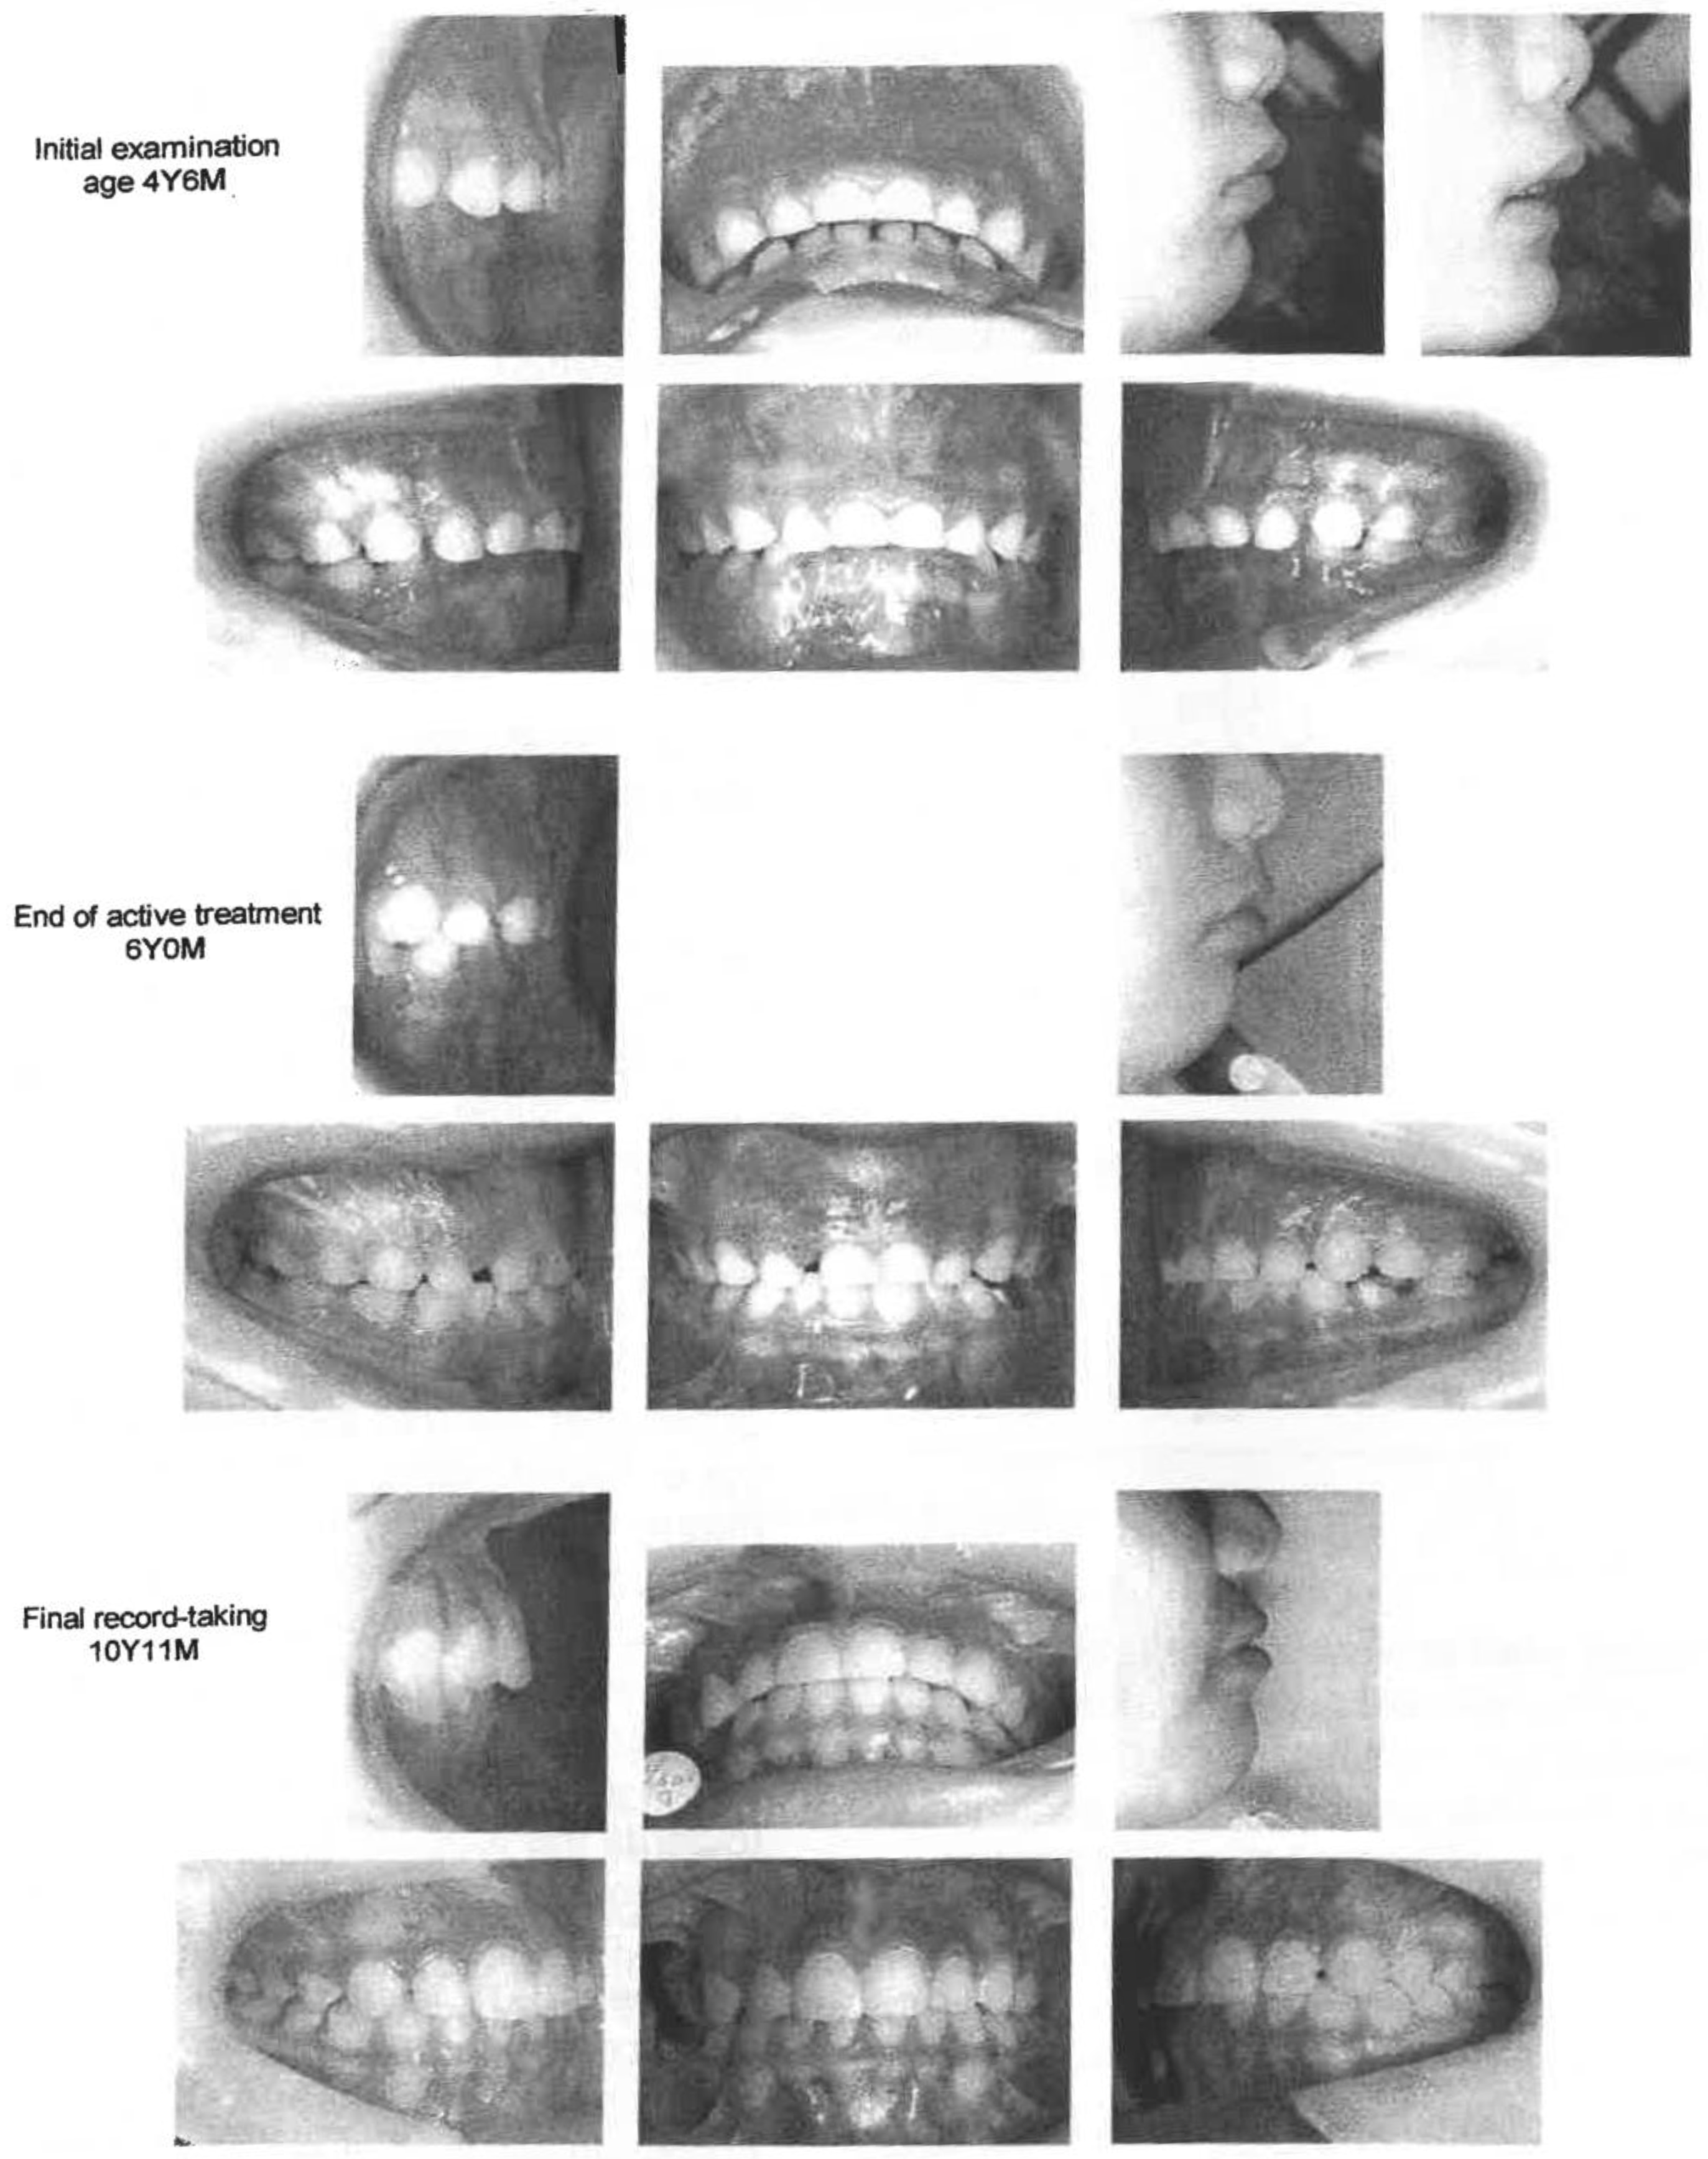

Figure 8. Case 2 - Functional Appliance.

In Phase I, F.A. was worn to retrocline the upper deciduous incisors, procline the lower deciduous incisors and stimulate forward mandibular growth (Figure 8). F.A. was constructed to achieve about 3mm of open bite and unforced forward positioning of the mandible. The appliance was adjusted every month or two. The child was instructed to wear F.A. as much as possible during the day as well as at nighttime. The lip sucking and lip biting habits were eliminated in 4 to 5 months. F.A. was left in place as a retainer until muscle function adapted to the new mandibular position. Mild crowding occurred in the lower anterior area in the mixed dentition. Another F.A. with screws was fabricated and worn for lateral expansion of the upper and lower arches.